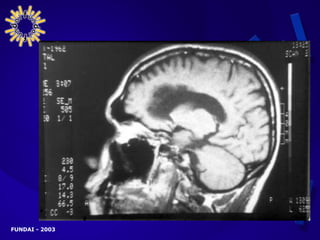

MANIFESTACIONES CLÍNICAS AVANZADAS   PRESENTACIÓN NEUROLÓGICA CENTRAL Cefaleas Fiebre Trastornos de conciencia Convulsiones Rigidez de nuca Signos meníngeos Signos focales